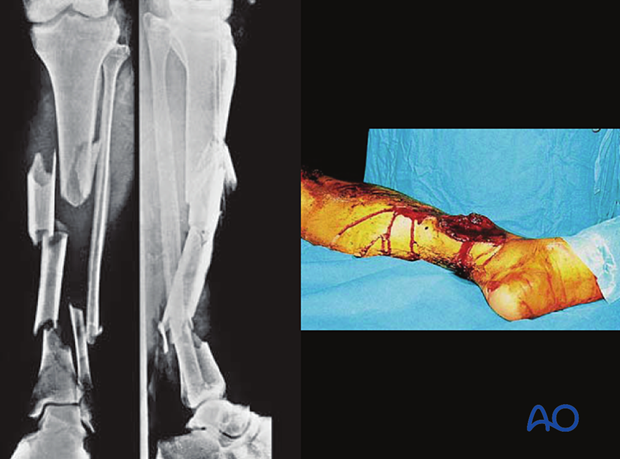

Intramedullary (IM) nailing can be chosen to manage open, complex fractures of the tibia. These images show a severe open segmental tibial fracture, in which IM nailing was performed.

If IM nailing must be delayed (due to significant wound contamination, etc.), temporary external fixation can be used for preliminary stabilization.